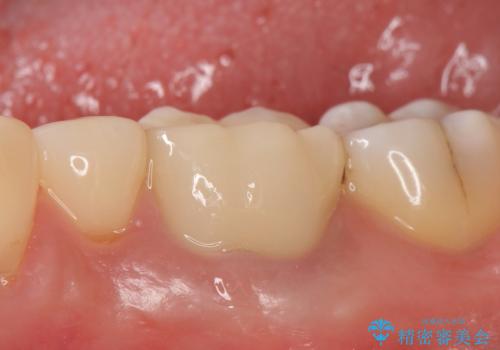

再根管治療終了後、オールセラミッククラウンにて補綴を行いました。

今回用いたオールセラミッククラウンはジルコニアフレームという白い素材の上にセラミックを盛っているため、審美性が非常に高いのが特徴です。

また、ジルコニアは人工ダイヤモンドの材料にも使われているほど高い強度を持っており、そのためオールセラミッククラウンは審美性だけでなく、奥歯やブリッジの補綴も可能とするクラウンです。